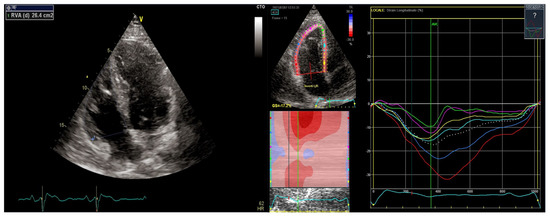

Abstract

3.1. Right Ventricular Dilatation

3.3. Speckle and Feature Tracking

3.4. Contraction Delay